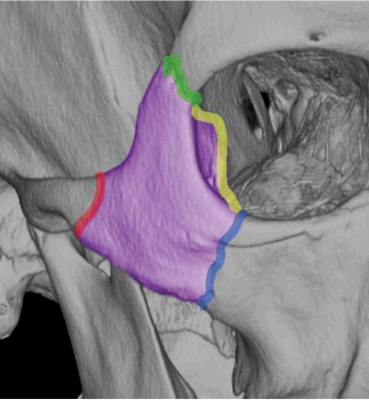

Трехмерное КТ-изображение с цветными накладками очерчивает костную анатомию скуловерхнечелюстного комплекса: скулолобный (зеленый), скулоклиновидный (желтый), скуловерхнечелюстной (синий) и скуловисочный (красный) швы вокруг скуловой кости (фиолетовый).